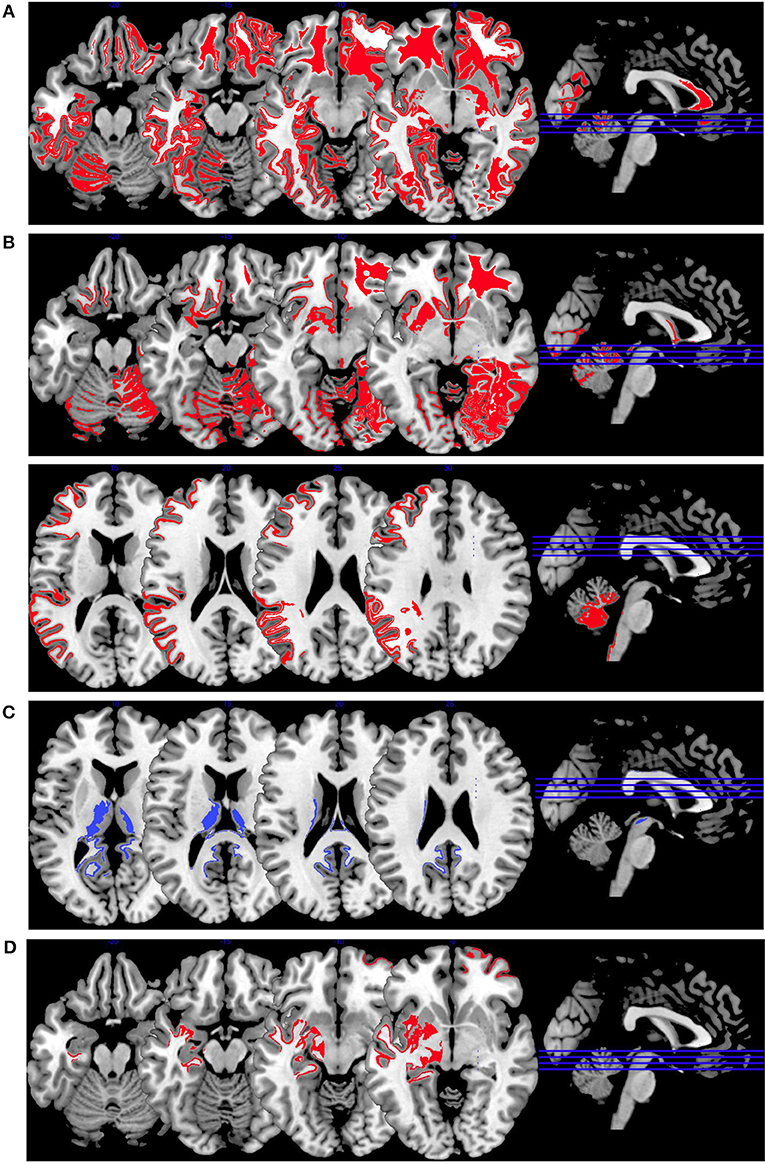

In Figure 2, we provide an overview on working memory activation patterns over all reviewed studies. As shown in Figure 2A, violent as opposed to non-violent persons with schizophrenia showed hypoactivation in the right inferior parietal lobe. This is an area known for being part of the working memory network, but it has until now not been observed in specific aggression paradigms. The hypoactivation seen in this group comparison may therefore not be specific for aggression, but may represent working memory dysfunction in the VS group.

Figure 2. Working memory activations. Overview of the working memory brain activation patterns reported by the reviewed studies. Hyperactivations are shown in red, hypoactivations in blue. (A) shows the activation patterns in the group comparison VS vs. NVS with VS<NVS in blue (shown slice numbers are 210, 220, 230, 240) in the contrast 2-back vs. 0-back, (B) shows the activation patterns in the group comparison VS vs. HC with VS>HC in red (shown slice numbers are 170, 180, 190, 200) in the contrasts 1- and 2-back vs. 0-back and cognitive (go/no-go task) vs. reference condition and VS<HC in blue (shown slice numbers are 160, 170, 180, 190) in the contrast NoGo20 vs. NoGo40 and NoGo40 vs. Go and cognitive (go/no-go task) vs. reference condition, (C) shows the activation patterns in the group comparison NVS vs. HC with NVS>HC in red (shown slice numbers are 170, 180, 190, 200) in the contrast 1- and 2-back vs. 0-back.

Figure 2B shows hyperactivations of VS as compared to HC mainly in the frontal lobe and in the middle temporal gyrus. In addition, we see hypoactivations of VS as opposed to HC in the right middle frontal gyrus, the cingulate gyrus, and in the superior temporal gyrus. As frontal regions are typically involved in working memory tasks, this finding is in line with the literature.

In Figure 2C, we present the activation patterns of NVS as compared to HC. NVS hyperactivate the left caudate nucleus and precuneus. The precuneus is known to be involved in working memory processes, while the caudate nucleus usually is not. Still, the latter—as a feedback processor—might be under higher workload conditions while solving these tasks in persons with schizophrenia than in healthy controls. Also, this could be an indicator toward the hypothesis that schizophrenia patients solve working memory tasks differently, namely trying to use information from past experiences to influence their decisions in the tasks.

Synthesis of Findings From Studies Using Emotion Induction Paradigms

In Figure 4, we provide an overview on activation patterns during emotion induction over all reviewed studies. As with the other multislice activation pattern figures, this can be helpful to enable a synthesis of findings across the published studies. However, the emotion induction tasks used in the different studies vary considerably, and therefore this synthesis of the findings may be of limited use and must be interpreted with caution.

Figure 4. Emotion induction activations. Overview of the working memory brain activation patterns reported by the reviewed studies. Hyperactivations are shown in red, hypoactivations in blue. (A) shows the activation patterns in the group comparison VS vs. NVS with VS>NVS in red (shown slice numbers are 100, 110, 120, 130) in the contrasts shock anticipation phase II (last 21 s after threatening with an electric shock) vs. shock anticipation phase I (first 9 s after threat) and negative vs. neutral emotional pictures and neutral emotional pictures vs. rest, (B) shows the activation patterns in the group comparison VS vs. HC with VS>HC in red (shown slice numbers are 100, 110, 120, 130) in the contrasts shock anticipation vs. safe condition and in negative vs. neutral emotional pictures contrast and neutral emotional pictures vs. rest, (C) shows the activation patterns in the group comparison NVS vs. HC with NVS>HC in red (shown slice numbers are 170, 180, 190, 200) in the contrast negative vs. neutral emotional pictures and NVS<HC in blue (shown slice numbers are 160, 170, 180, 190) in the contrast positive vs. neutral emotional pictures, (D) shows the activation patterns in the group comparison NVS high vs. low aggression with NVS high>NVS low in red (shown slice numbers are 100, 110, 120, 130) in the contrast of hearing emotional words (positive and negative ones) vs. rest.

Figure 4A shows the group comparison of violent vs. non-violent persons with schizophrenia over all emotion induction tasks. Only hyperactivations in the right middle frontal gyrus, inferior frontal gyrus, medial prefrontal gyrus, anterior cingulate, lingual gyrus, globus pallidus, mid-cingulate, precuneus, cuneus, middle temporal gyrus, inferior temporal gyrus and in the left middle occipital gyrus, and cerebellar tuber were reported in this group comparison.

When comparing VS with HC, as shown in Figure 4B, only hyperactivations can be found. Mainly, the right hemisphere is activated (middle frontal gyrus, parahippocampal gyrus, middle occipital gyrus, anterior cingulate gyrus, cuneus, superior parietal gyrus)—hyperactivations are also seen bilaterally in the superior frontal gyrus, lingual gyrus, fusiform gyrus, superior temporal gyrus and in the left precentral gyrus, caudate nucleus, postcentral gyrus, and inferior occipital gyrus. When comparing NVS with HC (Figure 4C), there were hyperactivations in the left cerebellum and the left inferior parietal lobe and a hypoactivation in the lingual gyrus.

The activation patterns in Figure 4C differ considerably from the ones shown in the group comparison VS vs. HC in Figure 4B—we therefore suspect that emotion networks in particular may play an important role in patients with schizophrenia and aggression when in comparison with NVS. However, further studies with higher methodological quality and replication studies using comparable emotion induction paradigms are needed to test this hypothesis.

When comparing high vs. low aggressive NVS in emotion induction paradigms (Figure 4D), authors reported hyperactivation in the right superior frontal gyrus and the left hippocampus. However, it remains unclear whether these activation patterns are specific for aggression.

Synthesis of Findings From Studies Using Affective Theory of Mind Paradigms

In Figure 5, we provide an overview on activation patterns generated by affective theory of mind paradigms. The only study reporting on this area was performed by Schiffer et al. (36). Hyperactivations were present in the left inferior frontal gyrus and the left superior temporal sulcus reported in the group comparison of violent as opposed to non-violent persons with schizophrenia. Here, activation of the inferior frontal gyrus is compatible with a challenge in language comprehension, while the superior temporal sulcus is known to be implicated in social perception and general theory of mind.

Figure 5. Affective theory of mind activations. Overview of the affective theory of mind brain activation patterns reported by the reviewed studies, the group comparison being VS vs. NVS in the contrast of mental state attribution vs. gender discrimination. Here, we show the hyperactivation of VS>NVS in red (shown slice numbers are 170, 180, 190, 200).